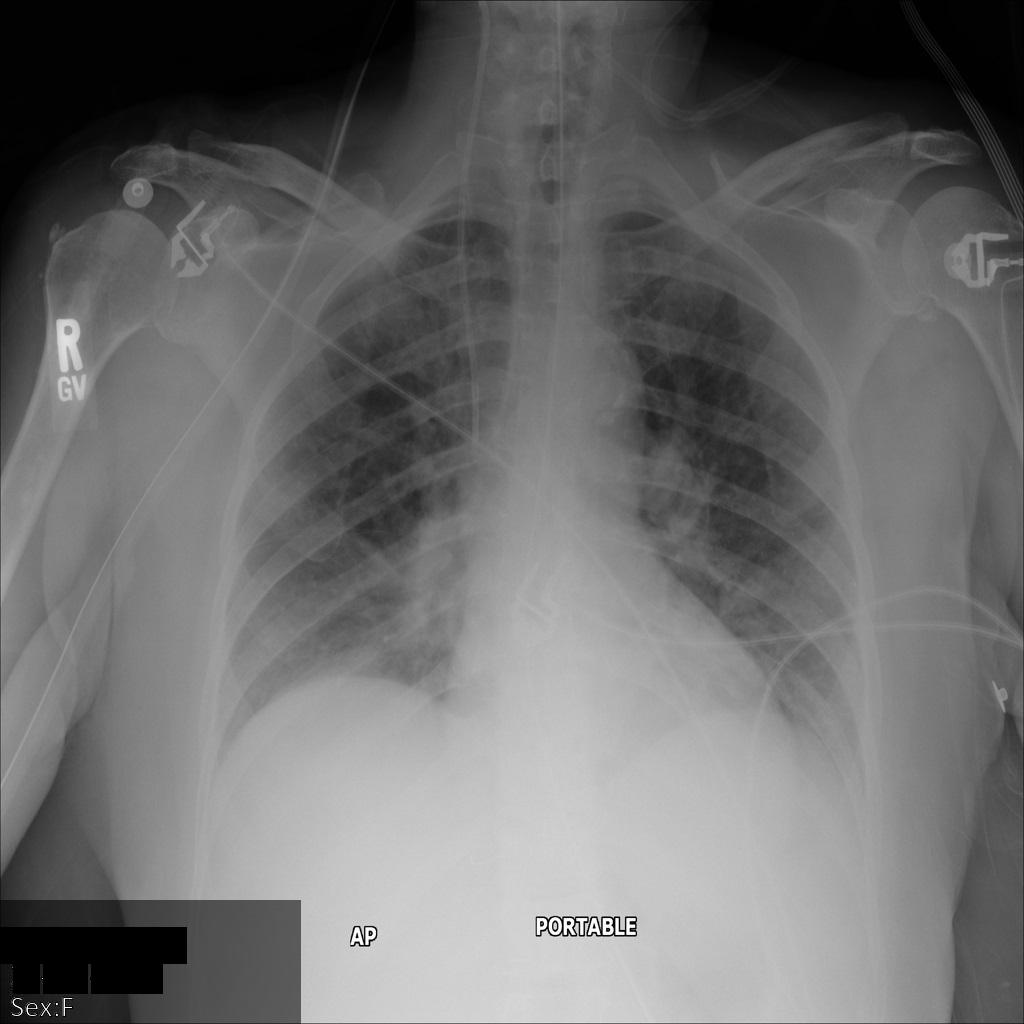

Dopo aver inviato l'immagine all'API Cloud Healthcare utilizzando

l'opzione REDACT_SENSITIVE_TEXT, l'immagine

viene visualizzata nel seguente modo:

Puoi notare che si è verificato quanto segue:

- Il

PERSON_NAMEin basso a sinistra dell'immagine è stato oscurato - Il

DATEin basso a sinistra dell'immagine è stato oscurato

Il sesso del paziente non è stato oscurato perché non è considerato testo sensibile secondo i tipi di informazioni DICOM predefiniti.